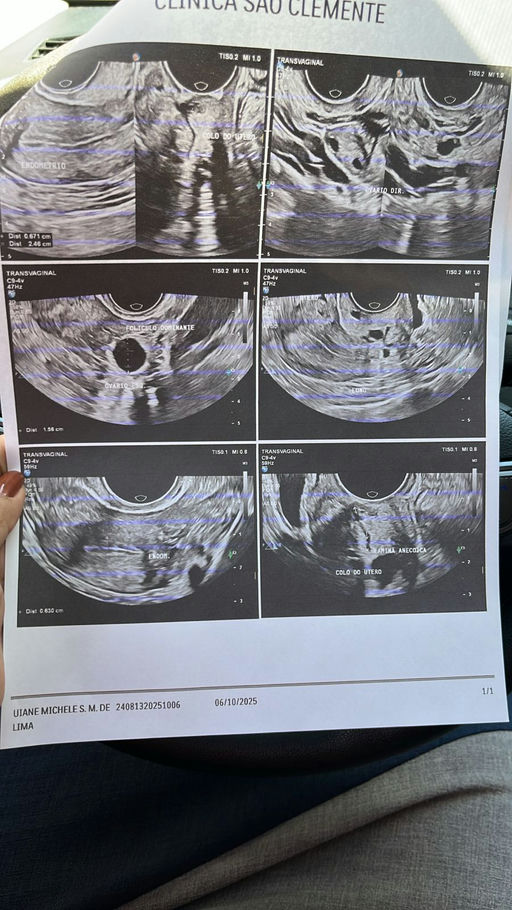

Uiane

Oct 6, 2025

Resultado da US de hoje Estou em uso do fostimon 75ui